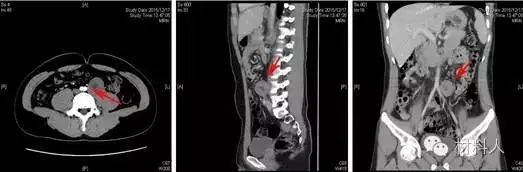

1.術前規劃

對于骨折患者,尤其是復雜骨折患者,術前有實體解剖模型用于分析或模擬手術操作較單純依靠二維平面的MRI或CT掃描更具指導意義(圖2)。

術前應用3D打印技術可使醫生對患者的病情有更加直觀的認識,尤其是對經驗不夠豐富的年輕醫生,更有利于疾病的診治。

臨床結果表明使用3D模型組較非3D模型組手術時間更短、術中出血量及術后引流量更少,有利于骨折的精確復位,提高手術精度、縮短手術時間,達到更好的手術效果。

圖3 骨盆(上)與肩部(下)惡性骨腫瘤利用3D打印技術進行術前規劃。打印腫瘤模型,呈現腫瘤切除邊界

圖片來源:網絡公開資料

【醫學應用】2016年1月,北京清華長庚醫院神經外科主任王貴懷教授于神經外科上演了一幕“刀尖上的華爾茲”,他利用3D打印技術,“克隆”患者病變部位腰椎模型,精準地呈現了患者腫瘤與椎體、血管及輸尿管的分布和形態,精準實施腫瘤切除手術。